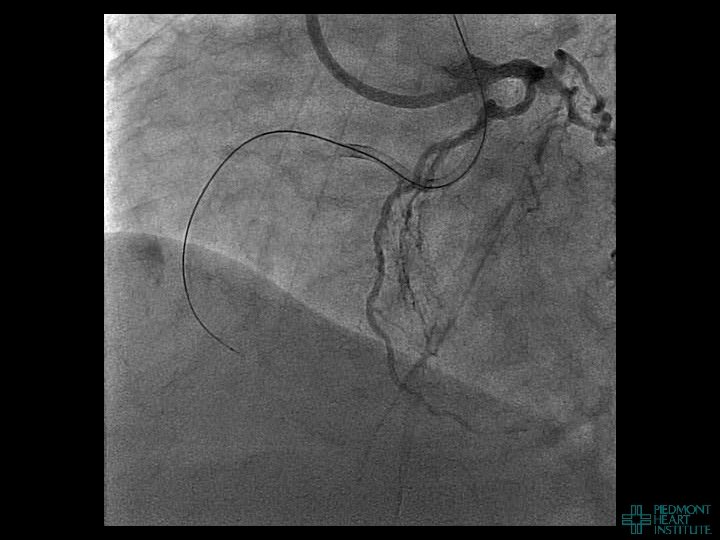

Case Example 3

Day 2 Stable overnight No further pericardial drainage Echo shows no recurrence of effusion

Day 2 Stable overnight No further pericardial drainage Echo shows no recurrence of effusion In ICU, pericardial pigtail catheter pulled…. . Within 5 minutes, systolic blood pressure drops to <80 and bedside echo confirms recurrence of effusion Emergency pericardiocentesis draws off 650 cc immediately followed by continuous drainage of blood